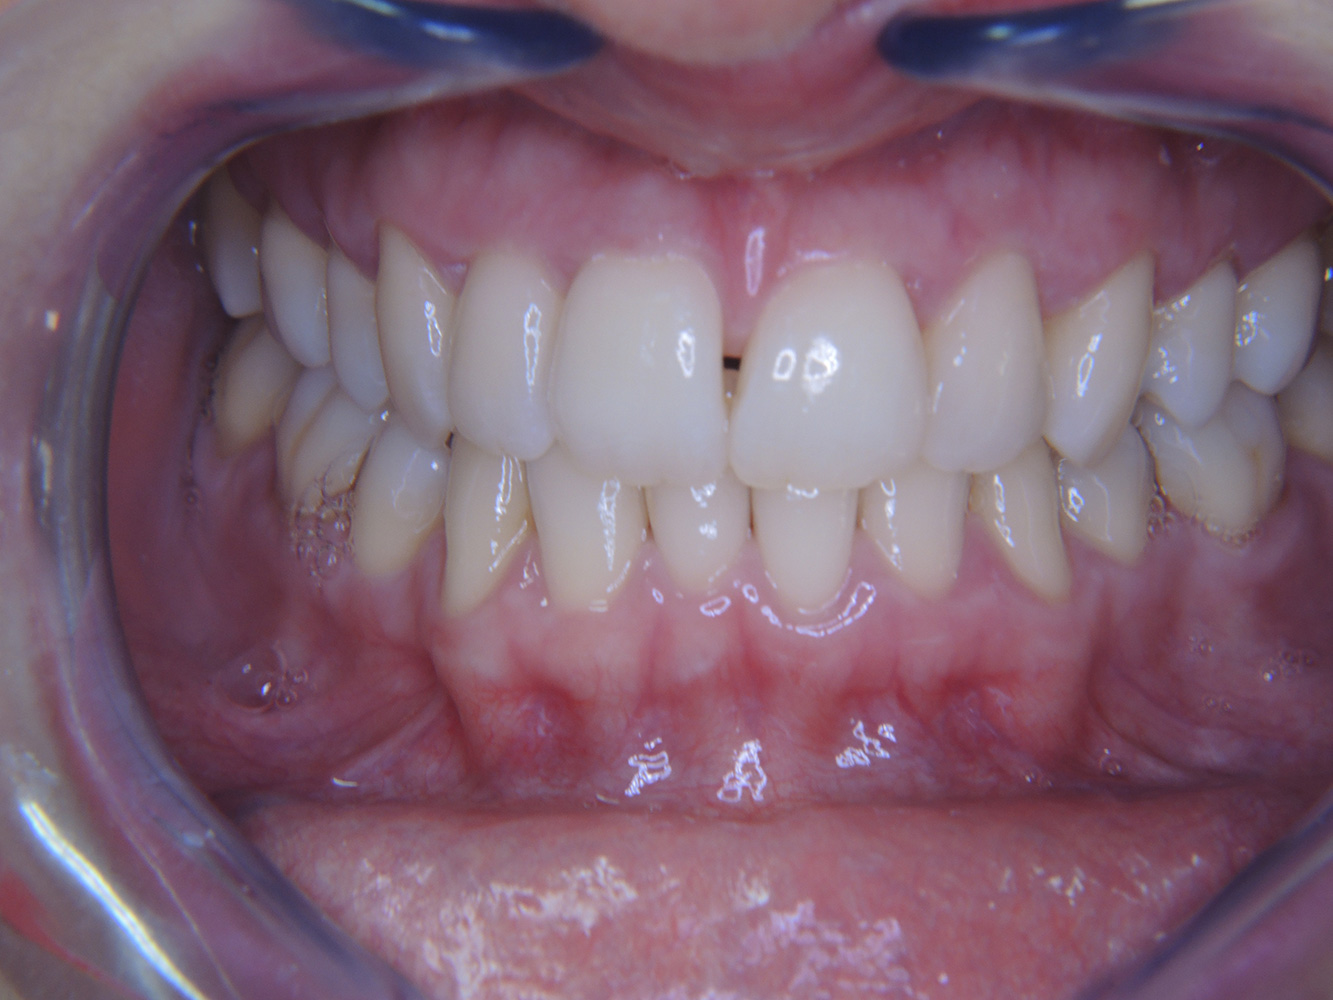

The healthy patient with pre-existing periodontal disease & peri-implantitis

A 52-year-old patient presents at a preventive care session. The patient has no systemic disease and is not taking any medication. He has had various dental treatments and also has two active carious lesions. In addition, the patient has four implants (2nd, 3rd and 4th quadrants). He is revealed to have early periodontal disease (stage IV, grade B). His periodontal condition is stable; a probing depth of Probing depths (ST) of 5 mm is only evident at the implant in region 36. Gingivitis is also identified. more